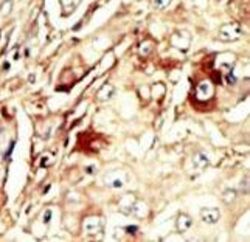

Immunohistochemistry

LS-C101210 IHC